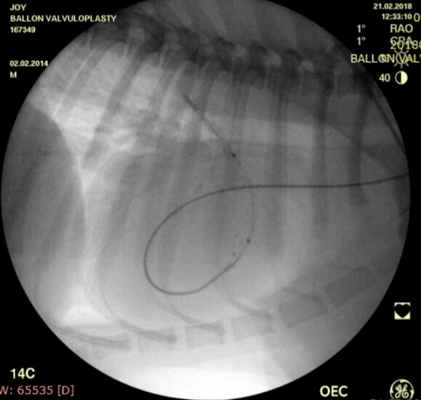

Показанием к оперативному лечению служит градиент систоличесокого давления на клапане легочной артерии свыше 50 мм рт.ст. При наличии дисплазии створок клапана — показана хирургическая коррекция порока, в остальных случаях возможно эндоваскулярное лечение. Операция выполняется в большинстве случаев под в/в анестезией, за исключением новорожденных, находящихся в критическом состоянии, у которых операция выполняется пол общим обезболиванием. Суть операции заключается в том, что после пункции бедренной вены в полость правого желудочка проводится и устанавливается катетер, далее проводник через клапан легочной артерии проводится в дистальные отделы легочной артерии. По проводнику в последующем проводится баллонный катетер и выполняется вальвулопластика. В настоящее время операция не сопровождается развитием летальных исходов и осложнений. Госпитальный период ограничен 3 днями.

Проведено: баллонная вальвулопластика клапана легочной артерии (Тип А). Баллон Cordis maxi 40х20 мм. Инфляция до 5 атм. 10 попыток.